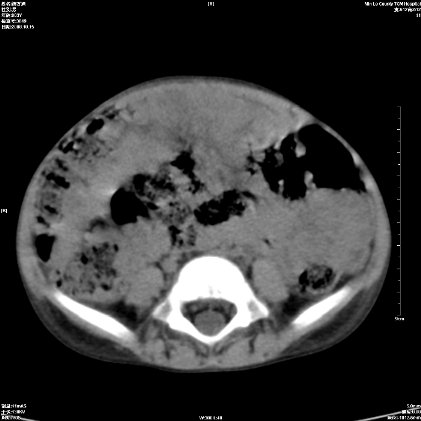

标题: PED1609:男性,3岁。彩超示肝Ca. [打印本页]

标题: PED1609:男性,3岁。彩超示肝Ca.

3岁;肝低密度灶;有钙化;有转移灶;考虑肝母细胞瘤;查afp

考虑后纵隔恶性畸胎瘤伴肝内多发转移可能性大,右侧肾上腺转移不除外

考虑后纵隔恶性畸胎瘤伴肝内多发转移可能性大,右侧肾上腺转移.

后纵隔恶性畸胎瘤,肝内多发转移可能性大,